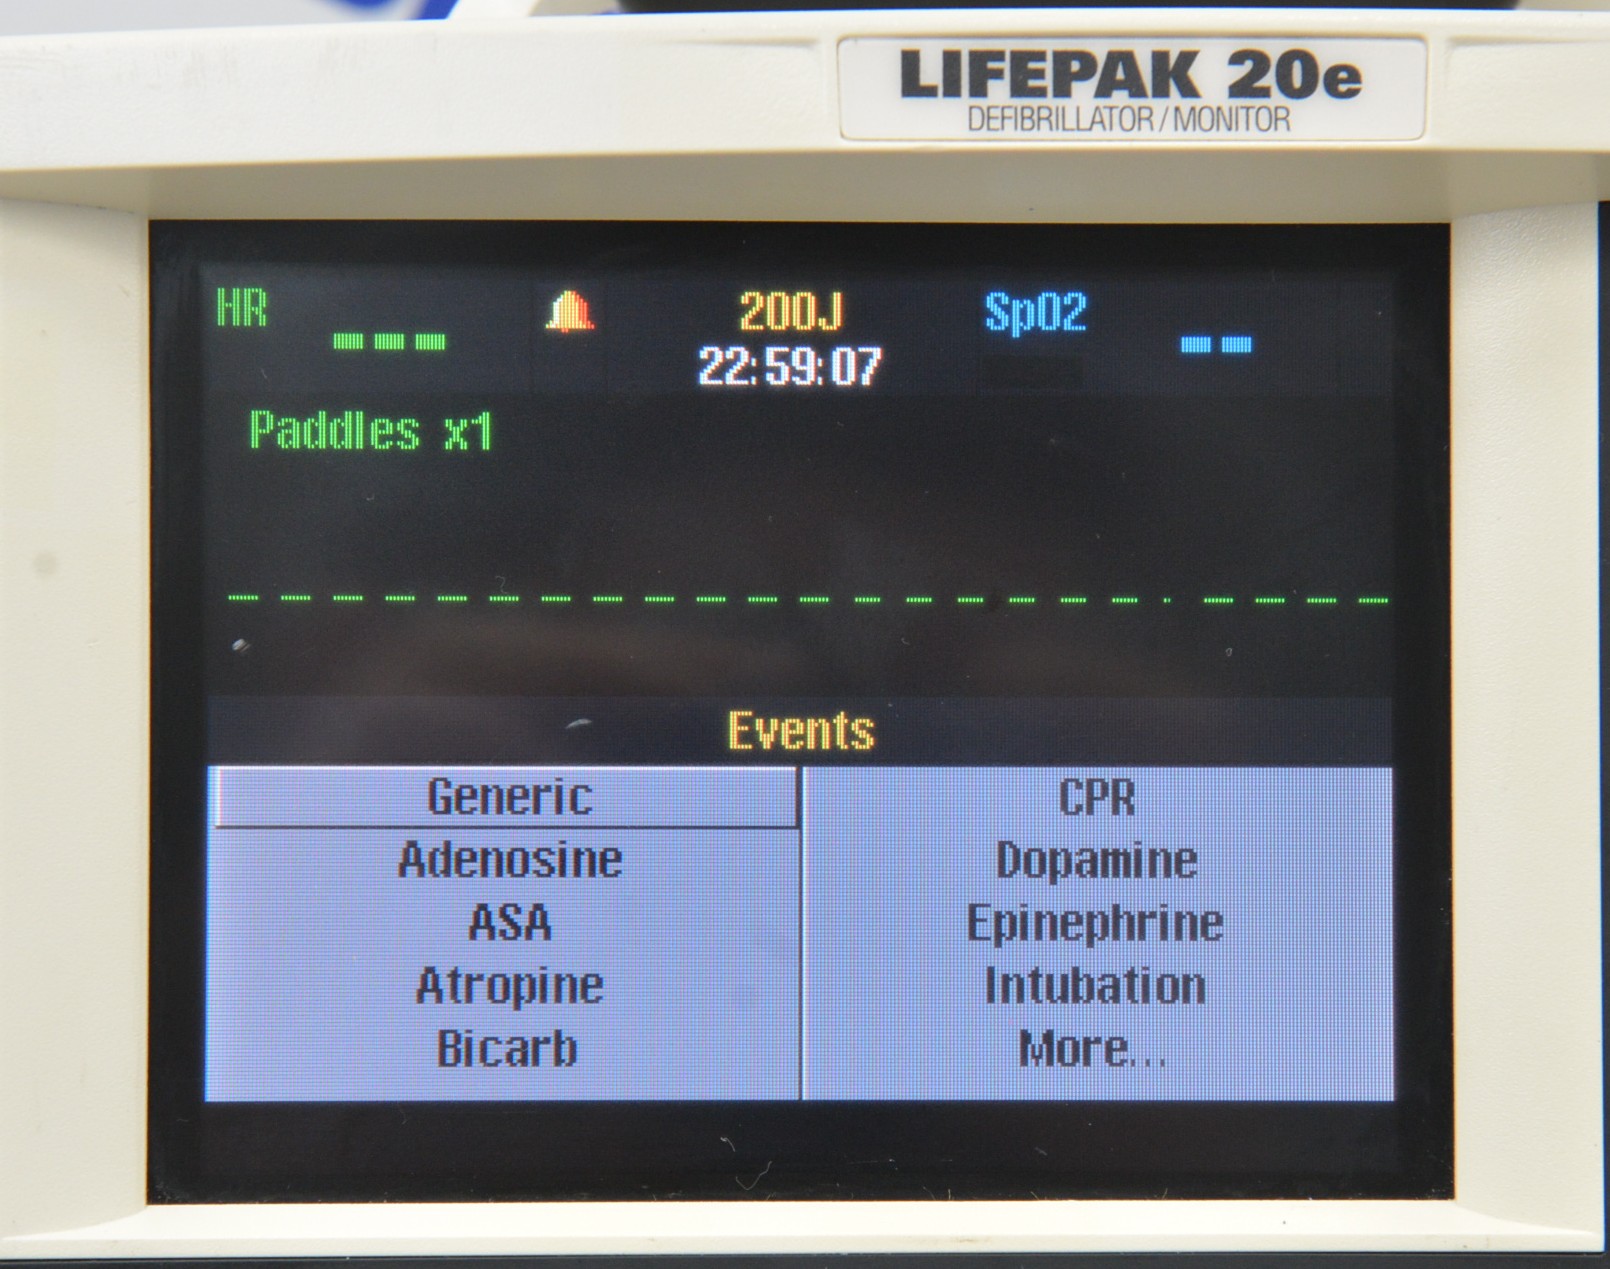

This Medtronic Lifepak 20e Defibrillator Monitor 2010 W/ Paddles is in good working condition. The unit powers on properly and responds to selections. All connection points are clean and in good condition. There are some scuff marks from previous use (see photos). This unit comes with a 30 day satisfaction guarantee. Includes everything in the pictures and nothing else.